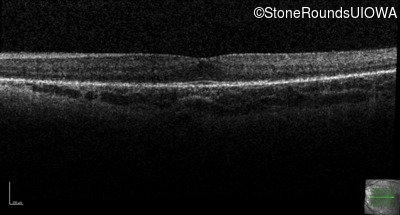

Optical Coherence Tomography - Right - 10/16 sc

Exemplar / OCT Stack